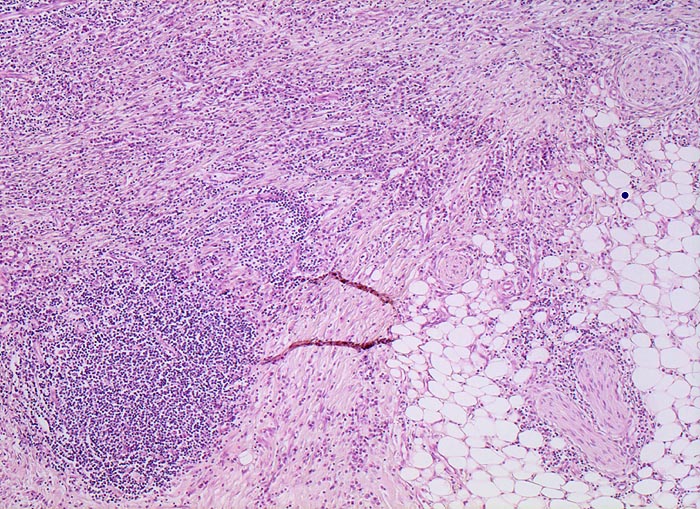

Morphologische Merkmale:

• Architekturstörung: Verplumpung und Abflachung der Dünndarmzotten. Verzweigte Krypten.

• Transmurale Entzündungsinfiltrate mit Lymphfollikelbildung.

• Zahlreiche epitheloid-riesenzellige Granulome in allen Wandschichten.

• Schlitzförmige fissurale Ulzera mit Vernarbung der umgebenden Submukosa.

• Verdichtetes lymphoplasmazelluläres Entzündungsinfiltrat in der Lamina proria.

Neutrophile Granulozyten in der Lamina propria (aktive Entzündung) und Gewebseosinophilie (vermehrte eosinophile Granulozyten in der Lamina propria).